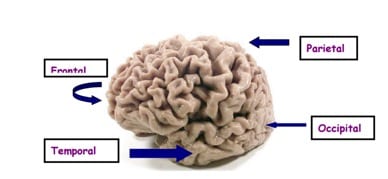

Cada hemisferio del cerebro está dividido en cuatro lóbulos:

- Frontal

- Parietal

- Temporal

- De ellos, el más trastornado es el temporal, y es precisamente este lóbulo quien controla muchas funciones importantes, incluyendo el lenguaje, la memoria, las emociones, la concentración y el sentido del tiempo y la individualidad